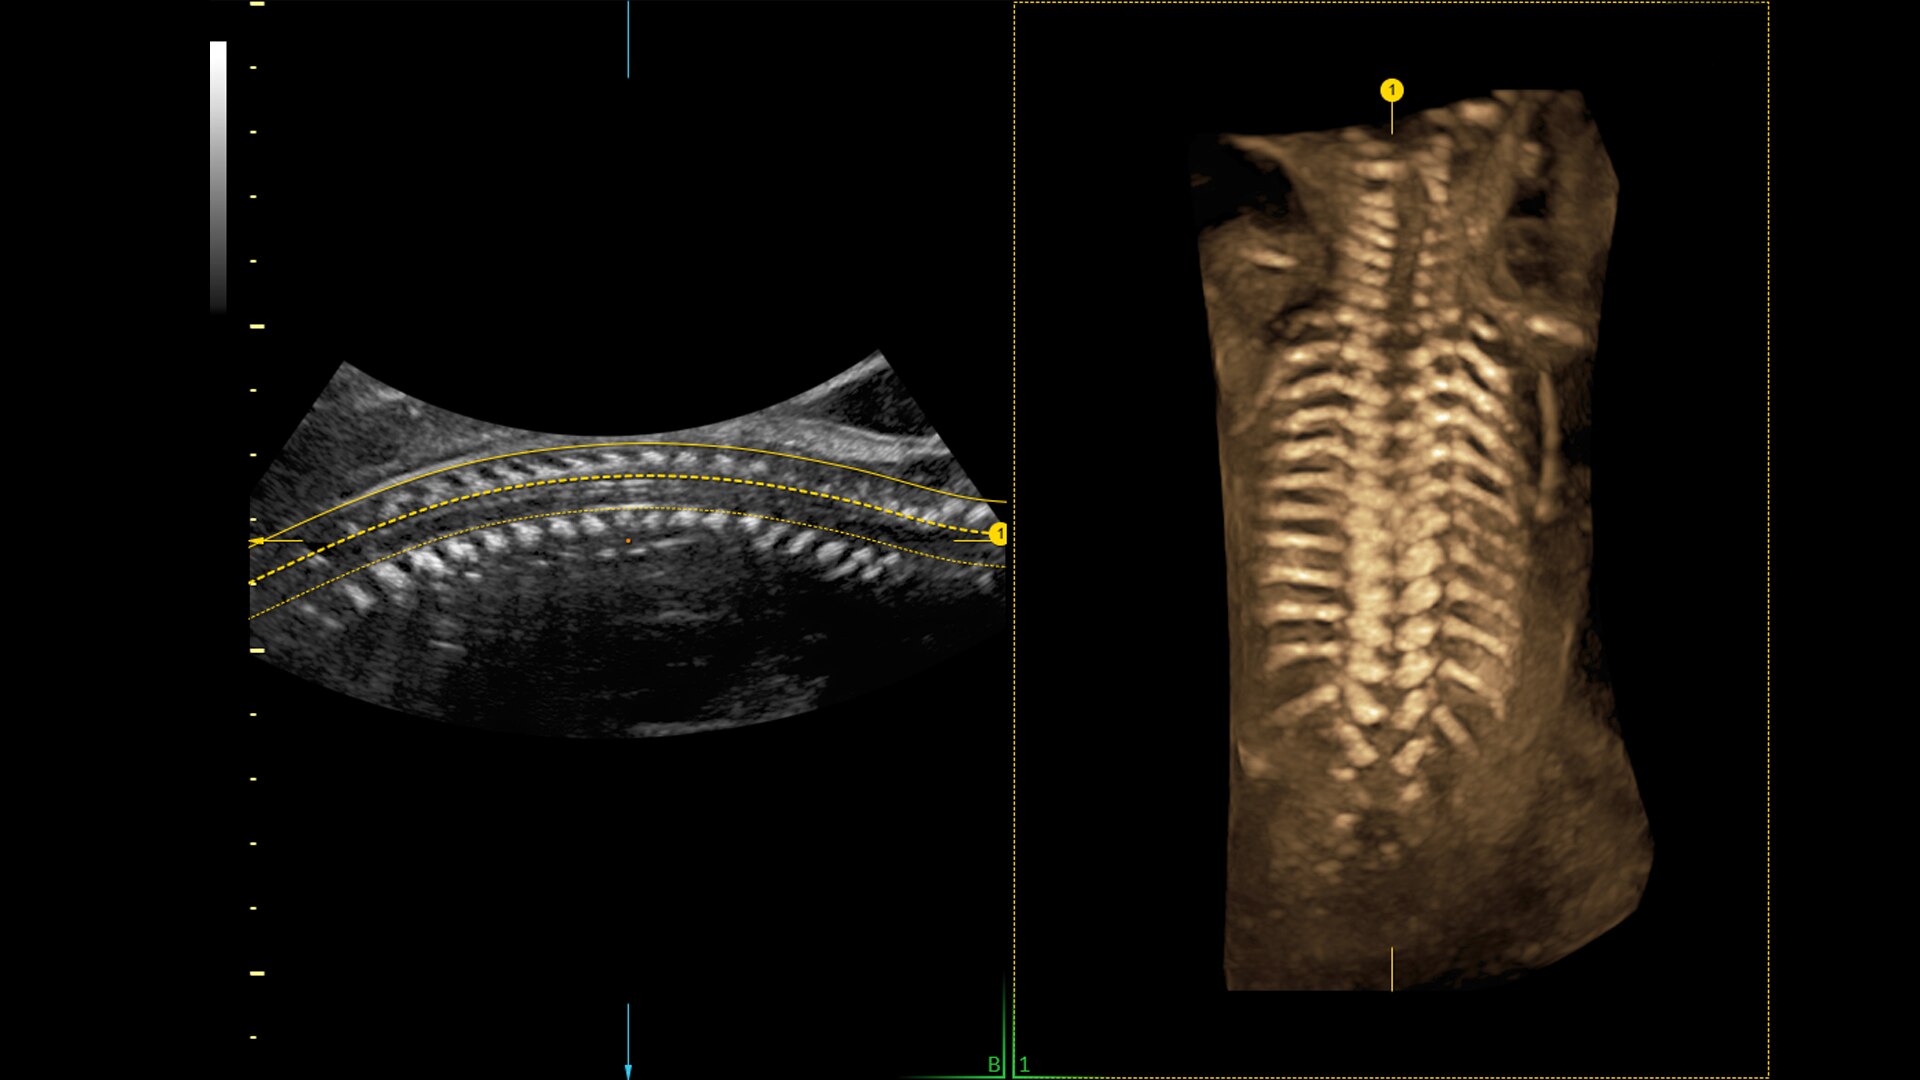

Spine Trace

Welcome to easy 3D in 1/2 the time. Simply trace the spine and the system automatically acquires the volume and displays the coronal view - with 83% less keystrokes.